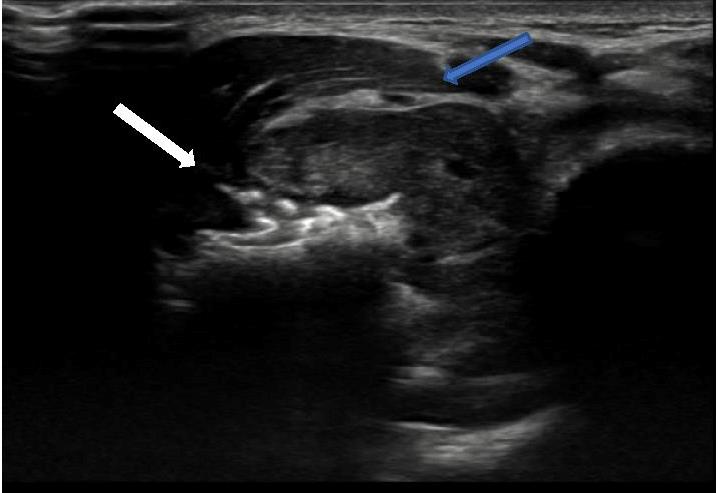

![]() |

Image C : Transverse image proximal ulna : spiculated tumour (white arrow) arising from right ulna with associated soft tissue mass, note preservation of fat plane between tumour & overlying muscle (blue arrow). |